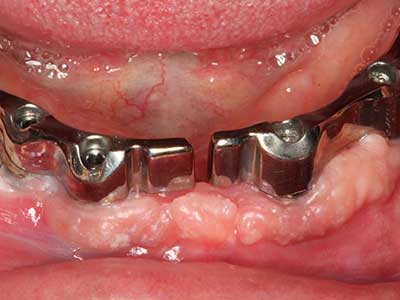

Como ya se ha demostrado en el pasado, básicamente cualquier procedimiento de cirugía de hueso representa una posible indicación para la cirugía piezoeléctrica. Así, la preparación del segmento móvil en la osteogénesis de distracción (fig. 23-25) y en la osteotomía de sándwich puede realizarse con piezas especiales, sin poner en peligro el suministro sanguíneo de la parte crestal, que resulta esencial para el éxito de ambas técnicas (González-García, Diniz-Freitas et al. 2008).

Para la extracción de implantes es posible realizar la preparación de una tapa ósea vestibular que, tras retirar el tornillo del implante, vuelve a fijarse y, de este modo, mantiene el contorno de la apófisis alveolar.